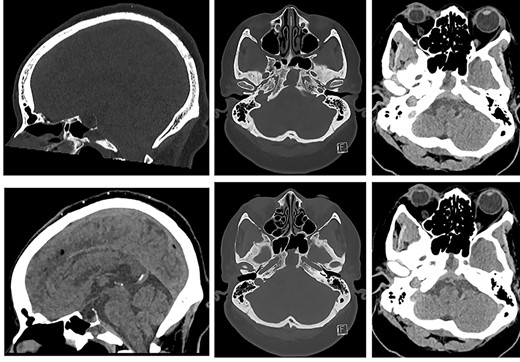

Due to ongoing symptoms, the patient underwent MRI 11 days post-operatively. This showed fluid-filled sphenoidal sinuses and clival osteomyelitis, extending intracranially to involve retroclival dura (Fig. 5).

![MRI of the head and orbits post-operatively (top row: sagittal T2WI and sagittal T1WI post-contrast; bottom row: axial T1WI post-contrast [from cranial to caudal]) showing fluid-filled sphenoidal sinuses, mucosal thickening and enhancement in the mucocele cavity, as well as persistent retroclival dural thickening.](https://oupdevcdn.silverchair-staging.com/oup/backfile/Content_public/Journal/jscr/2022/1/10.1093_jscr_rjab607/1/m_rjab607f5.jpeg?Expires=1778768511&Signature=AqFVCH2GWviwI8FGSpDNdNUhpZr9ZqLPO09SgQbH9lJkKESO1ddjPxYqTSTTJVHkhvJD-aua4lPSmPOmH0Bq889ovohLMAXyEx4p6AdRE0jqbr~Wh6ILbWQe-auYR6zX7J~cbPbNEJSTUIWfOr9xsvlQBT0~yI~KY5zwSQfRbJ9rkEKl~OhB-eLQ5y0xjuxEczsY-etuXuRwpbLVz6tXtDbEty0sqzcqvAqXIYVerYSIuqpRUOdP7-Ka7l0GBWltWHnG6xepIdbIIlTzhlHbwGnWXN0XDe9yTp4UqK1jSChcpdmTVoesbWDznAdOtTrFDBMkO-g9qPypV581gAjfMQ__&Key-Pair-Id=APKAIYYTVHKX7JZB5EAA)

MRI of the head and orbits post-operatively (top row: sagittal T2WI and sagittal T1WI post-contrast; bottom row: axial T1WI post-contrast [from cranial to caudal]) showing fluid-filled sphenoidal sinuses, mucosal thickening and enhancement in the mucocele cavity, as well as persistent retroclival dural thickening.